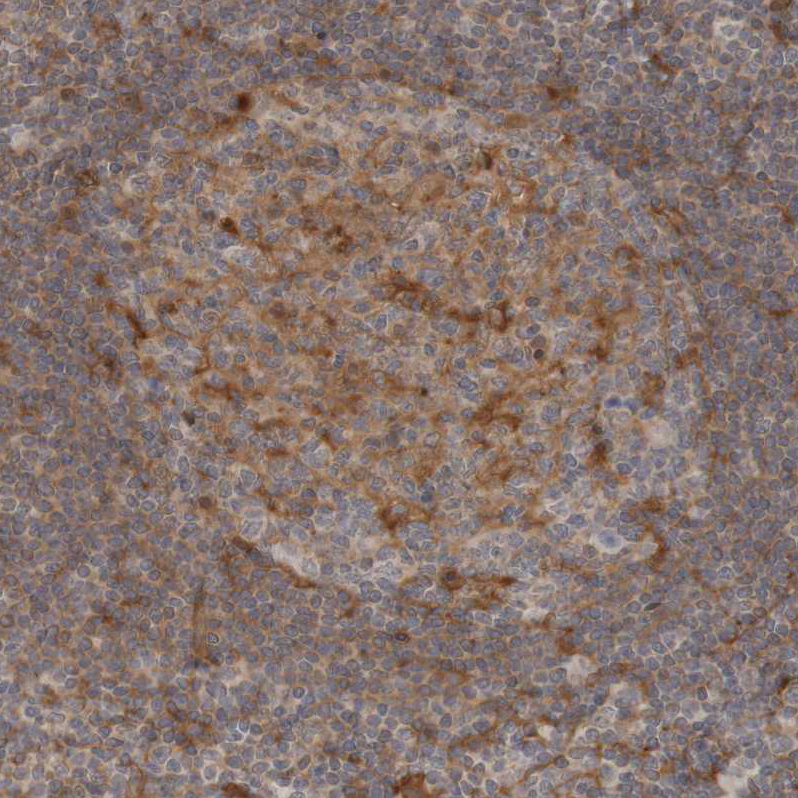

Immunohistochemical staining of human cerebral cortex, colon, testis and tonsil using Anti-ARHGEF11 antibody HPA011026 (A) shows similar protein distribution across tissues to independent antibody HPA014658 (B).